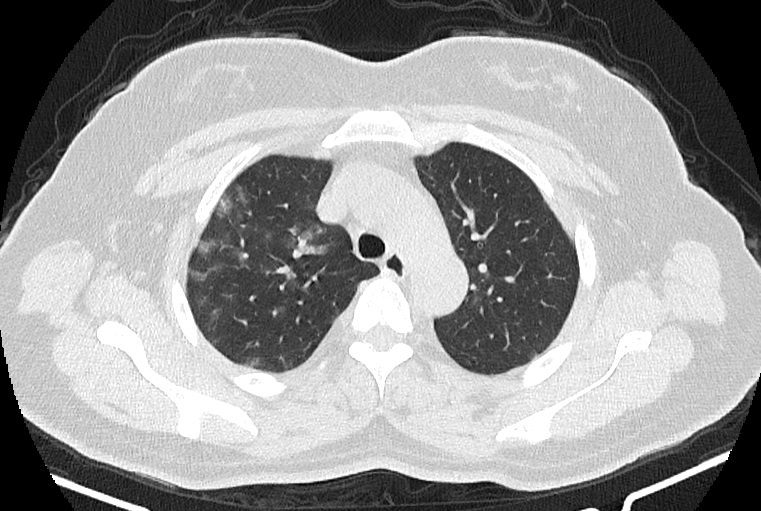

در HRCT از ريه ها(اسپيرال ، مولتي ديتکتور 16، مقاطع اگزيال با ضخامت 1mm بدون فاصله ) ، بدون كنتراست تزريقي :

-Ground glass opacities Patchy پراکنده در ريه ها مشهود است که مطرح کننده Viral pneumonia مي باشد . ( با درگيري 20 درصد حجم ريه )

نتیجه : Highly suggestive of COVID-19